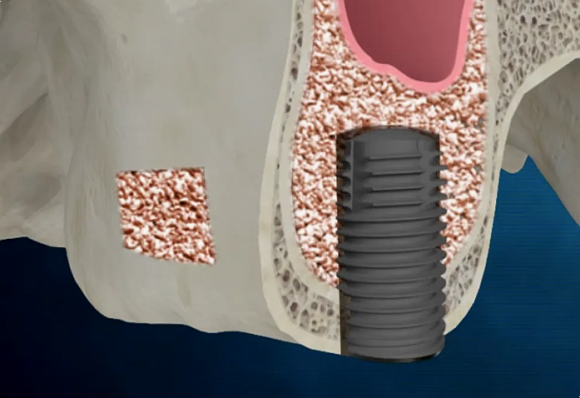

임플란트 식립

특히 상악동에 가까운 부위에서는 공기주머니인 상악동 내부의 막을 들어 올리고 그 아래에 인공 뼈를 넣는 과정이 추가로 필요하기 때문에 경험과 해부학적 지식이 풍부한 구강외과 전문의가 시술하는 것을 추천해 드립니다.

왼쪽 위 어금니는 발치 후 골이식과 상악동 거상술을 함께 시행했습니다.

수술 후 엑스레이에서 상악동이 인공 뼈로 채워진 모습이 확인되었고, 임플란트가 안정적으로 자리 잡았습니다.